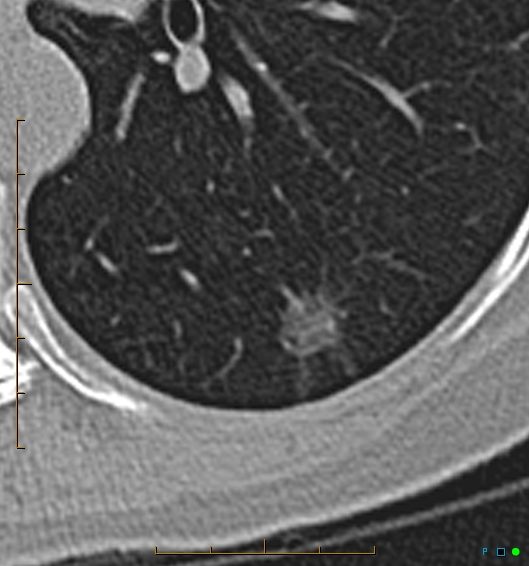

Il nodulo polmonare è un’opacità di dimensione < 3 cm, che non coinvolge la pleura, ed in genere non è associato a linfoadenopatia.

Per valutare il nodulo polmonare, vengono descritti dimensione, velocità di crescita ed alcuni aspetti morfologici :

• Densità. Può essere solida, a vetro smerigliato o parzialmente solida

• Forma. Nella maggior parte dei casi è rotonda o ovalare, ma può essere anche triangolare o poligonale (come spesso nel caso di linfonodi periscissurali), spiculati o stellati

• Margini. Possono essere lisci, lobulati o spiculati

• Contenuto. In caso di presenza di tessuto adiposo, calcificazioni o cavitazioni.

• Sono utili all’inquadramento del nodulo polmonare anche altri reperti come: retrazione pleurica, segno del broncogramma aereo, pseudocavitazioni, pattern cistico (raro) ed il vascular convergence sign.